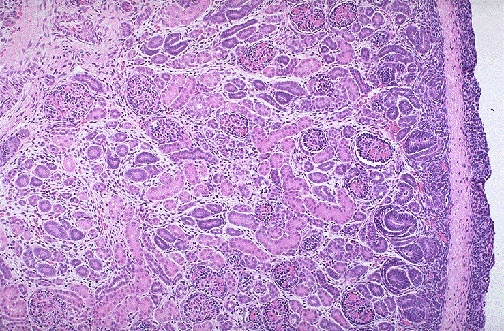

Image 3.7

Normal near-term infant kidney for comparison.